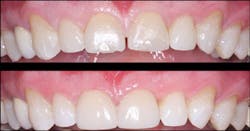

Veneers, where indicated and properly accomplished, technically have near-optimum esthetic appearance for many years (figures 5, 6). That is not the case with many PFM crowns, which often show unsightly margin exposure and loss of superficial stains after only a few years. With the popularity and increased use of lithium disilicate restorations, which do not have a metal substructure, this veneer advantage may not be as observable in the future.

Figure 5: Although these six anterior teeth had significant facial caries and discoloration and required facial and proximal reduction, they had intact lingual surfaces. Veneers instead of crowns were planned for the patient.

Figure 6: The six anterior ceramic veneers on the teeth have served the patient well for several years.